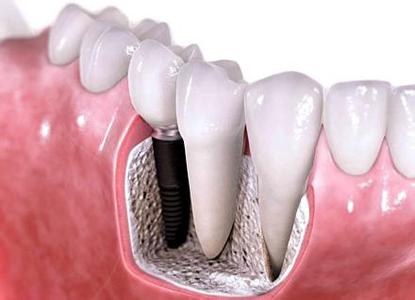

相比于传统修复方式需要必备的基托和卡环,种植牙就能更加方便,而且修复后的美观度也更好,清洁也更加方便,舒适感有所大大提升。

另外,种植牙还不需要磨牙,能够更好的保护健康的邻牙,而且能够像真牙一样扎根在患者的口腔中,不会出现牙齿绷瓷或是脱落的现象。